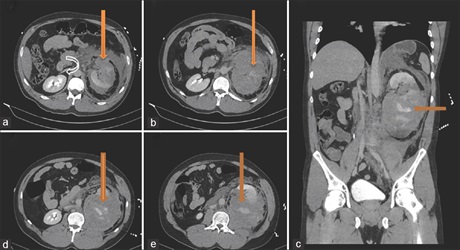

Kidney trauma occurs in approximately 1%–5% of all traumas with the male preponderance. The consequences of blunt renal trauma range from a simple contusion or renal hematoma to complete shattering of the organ or avulsion of the vascular pedicle. Recently, there is more focus on conservative management as newer techniques evolve and its currently the preferred approach to most renal injuries; however, surgery is the main treatment modality for avulsion of the renal pelvis, injuries to the vascular pedicle, and life-threatening hemodynamic instability. Renal artery embolization is a minimally invasive procedure used in the management of many disease conditions and also to control hemorrhage. We report of a Grade 5 renal injury with hemodynamic instability managed with renal artery embolization which otherwise would have been managed with surgery. A 33-year-old presented with Grade 5 left renal

injury and hemodynamic instability after a fall. Computed tomography of the abdomen after resuscitation showed shattered left kidney with disruption of the renal hilum and features suggestive of active bleeding. Due to the hypovolemic nature of the patient, embolization of the renal artery was requested. With anesthetic support and antibiotic cover, the right common femoral artery was punctured and a 5 French sheath inserted. Both left renal arteries were selectively catheterized and embolized to stasis with coils. An Angio-Seal device was deployed in the groin and no immediate complications seen. The patient was discharged few days after. This case report shows that Grade 5 renal artery can also be managed through a minimal invasive procedure to reduce the length of time at the hospital and also reduce the metabolic response of the patient.